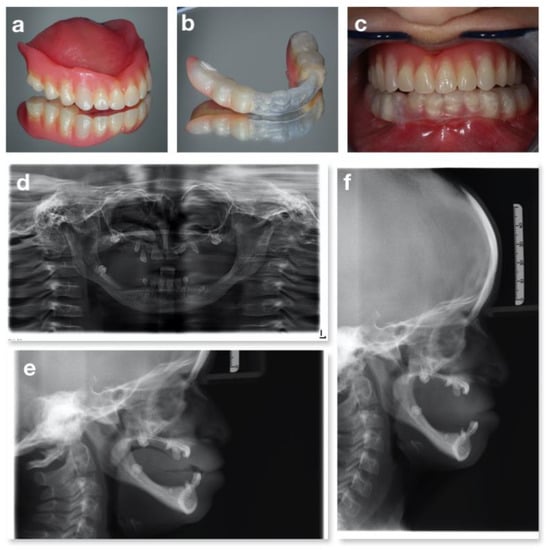

3.2. Congenital Nemaline Myopathies

3.3. CHARGE Syndrome